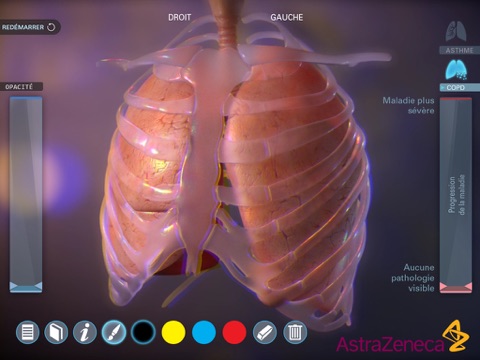

Living Lung est une application développée par AstraZenecaet destinée aux médecins. Elle présente en 3D lapparence des poumons des malades atteints dasthme ou de Broncho-Pneumopathie Chronique Obstructive (BPCO) en fonction de lévolution de la maladie.

Cette application, qui contient également des légendes anatomiques et un outil de dessin, est un support pour expliquer aux patients leur maladie.